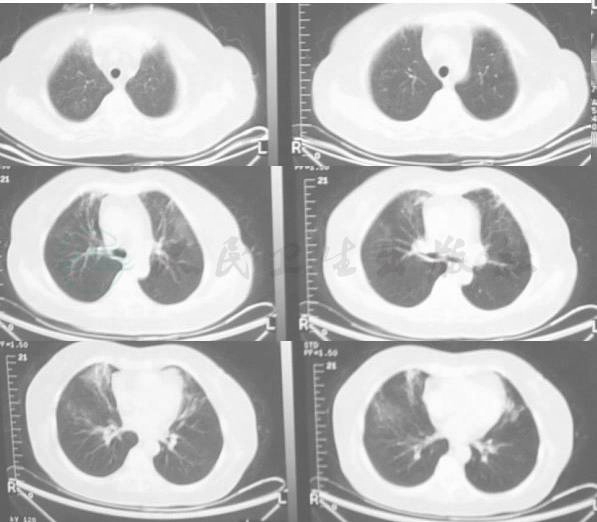

患者,女性,52岁,因“发热20余天,加重并出现呼吸困难1周”于2007年10月12日入院。患者于9月22日无明显诱因出现发热,体温38.5~39.2℃,自觉乏力、胸闷、头痛、头晕,纳差。自行服“阿莫西林、复方磺胺甲𫫇唑”等药物治疗无效。其后逐渐出现胸闷、咳嗽、气短。咳嗽较剧烈,以干咳为主,无咯血及脓痰。发病以来无明显盗汗,体温升高时有轻微关节疼痛,发热时面部有潮红,但未出现过皮疹。2周后体温进一步升高至39.5℃以上,予氨苄西林、利巴韦林等药治疗,效果不好。查血WBC 1.9×109/L,RBC 5.01×1012/L,Hb 140g/L,PLT 38×109/L。5天后体温进一步升高至40℃,胸X线示:双肺纹理增多,且出现呼吸困难(图1)。

图1 胸片(10月6日)示双肺纹理增多,双下肺密度轻度增高

4.肺部病变先为纹理增粗,条索状改变,继之为间质性变化,进行性加重,形成大片浸润和实变,双肺均衡受累,双上肺明显。抗感染、抗病毒、抗曲霉及激素治疗无效,病变迅速扩散;